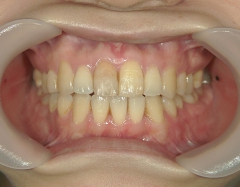

矯正歯科 治療後矯正歯科 プチワイヤー矯正 治療後矯正歯科(プチワイヤー矯正)治療後

矯正歯科 治療後  スペース確保の為、 2番抜歯

no.37_7548_治療後_右.JPGno.37_7548_治療後_正面.JPGno.37_7548_治療後_左.JPG